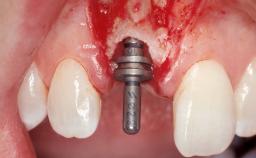

Late Placement of an Implant in a Maxillary Left Central Incisor Site

Type of Implants Two-Piece

Bone Augmentation Horizontal|Staged

Augmentation Materials Xenogenous|Membrane

Placement Protocol Early or late implant placement

Bone Volume Deficient horizontally, requiring prior grafting